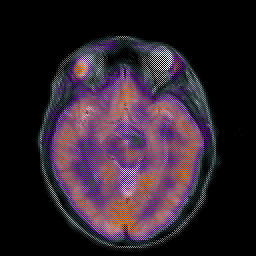

Hypertensive Encephalopathy, overlay -- Slice #10